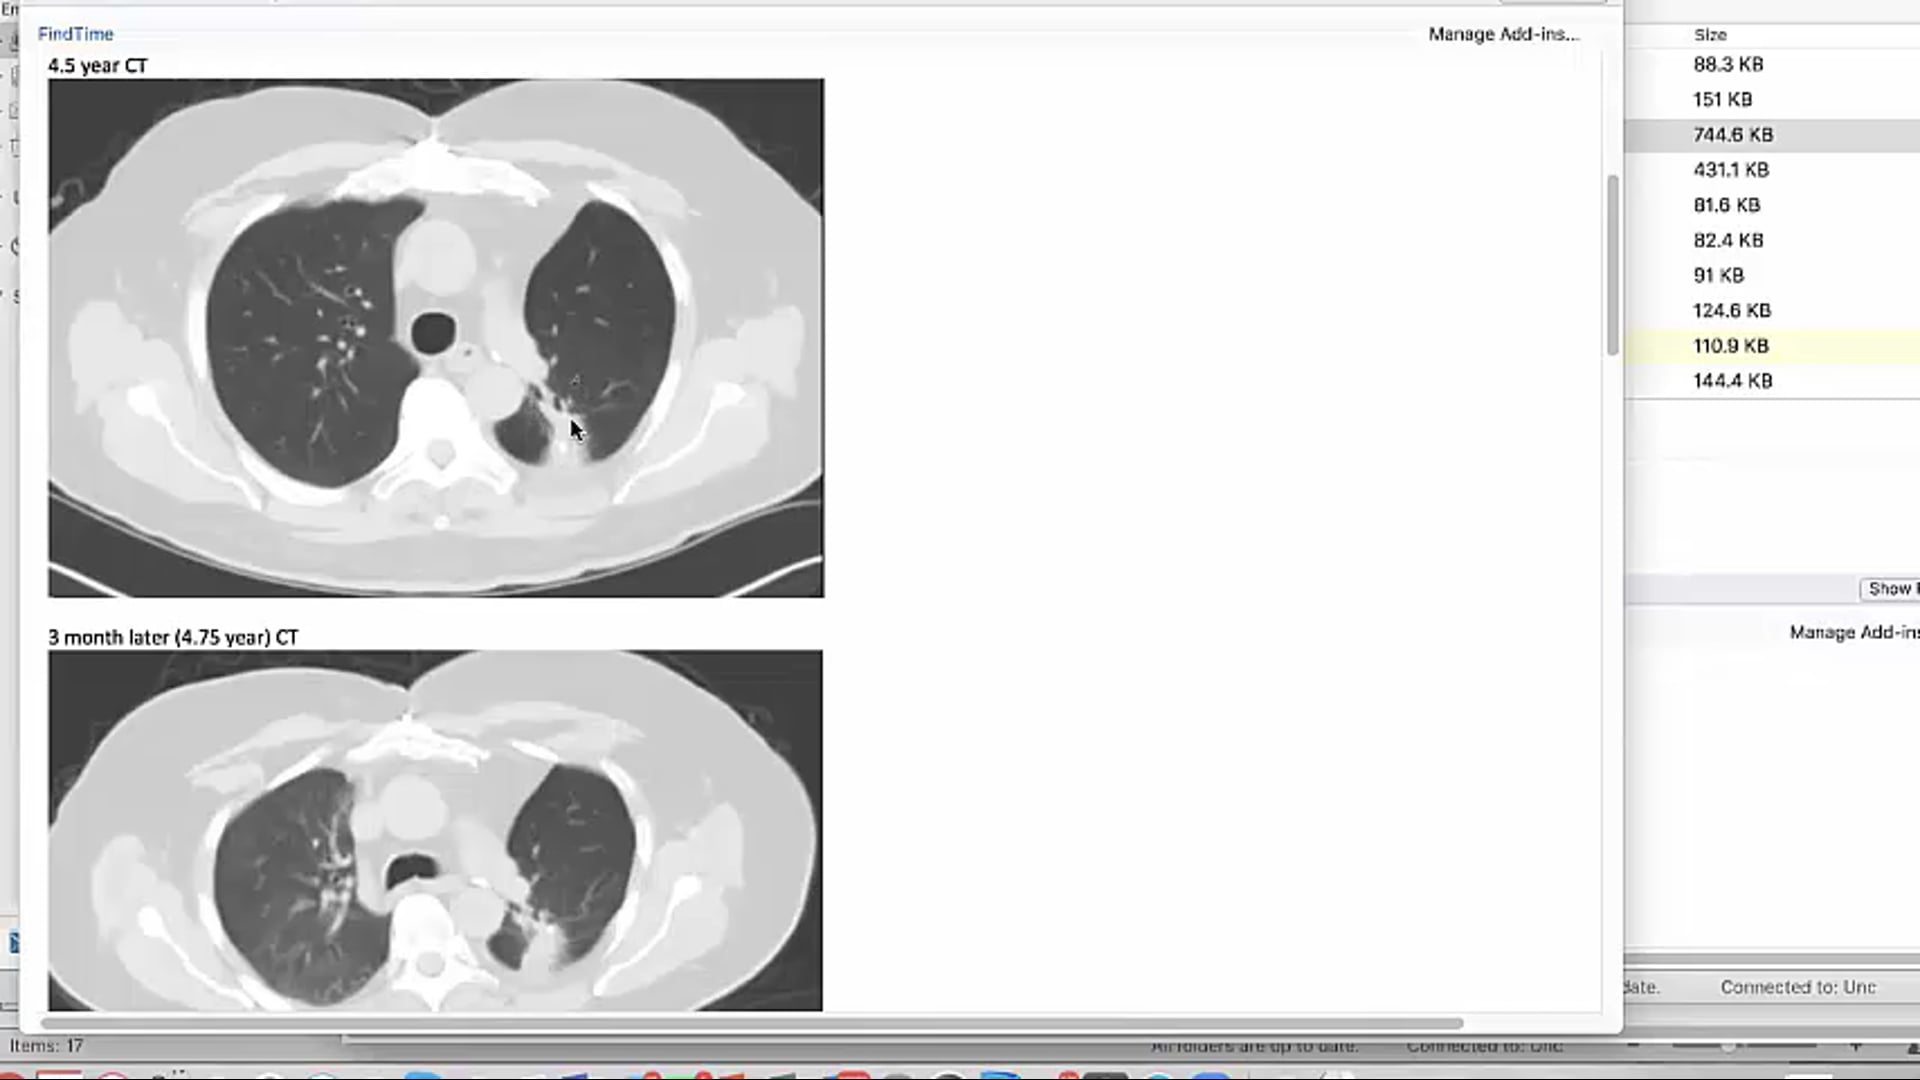

India SBRT Lung Sayan Paul August 10 2023 video edit